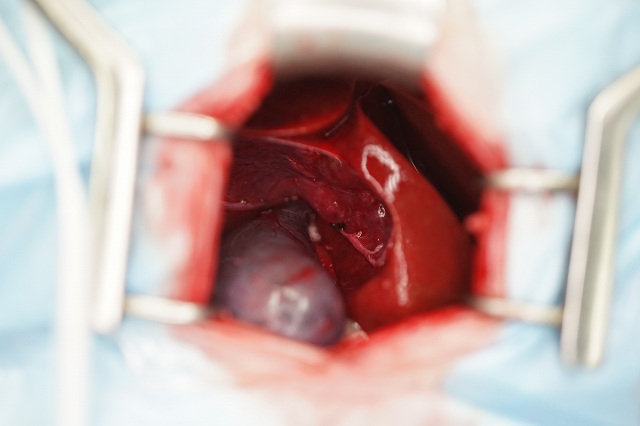

基本的には片側椎弓切除術による椎間板物質の摘出を行います。

椎間板の逸脱状況により、さらにアプローチを傷を小さくする場合もあります。

慢性炎症により肝臓への癒着が強い場合、胆嚢破裂を伴ったり、総胆管閉塞が強い場合は、開腹手術が適応になります。